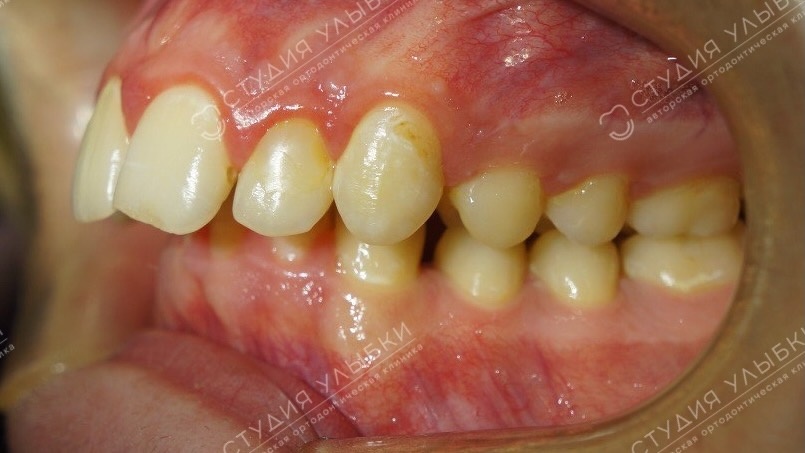

Фотопротокол — стандартные фотографии лица и зубов

Фотопротокол — обязательная часть диагностики перед брекетами у взрослых пациентов.

Для оценки линии улыбки делают фотографии — они показывают, насколько зубные ряды заполняют линию улыбки, какая высота уровня десны по отношению к зубам. Также оцениваются профиль лица и асимметрия.

Что включает фотопротокол:

• Лицо анфас и в профиль

• Улыбка в покое и при улыбке

• Положение зубов при смыкании

• Вид зубных рядов изнутри

Зачем нужен фотопротокол:

• Фиксация исходного состояния

• Контроль динамики лечения

• Выявление асимметрий и эстетических нюансов